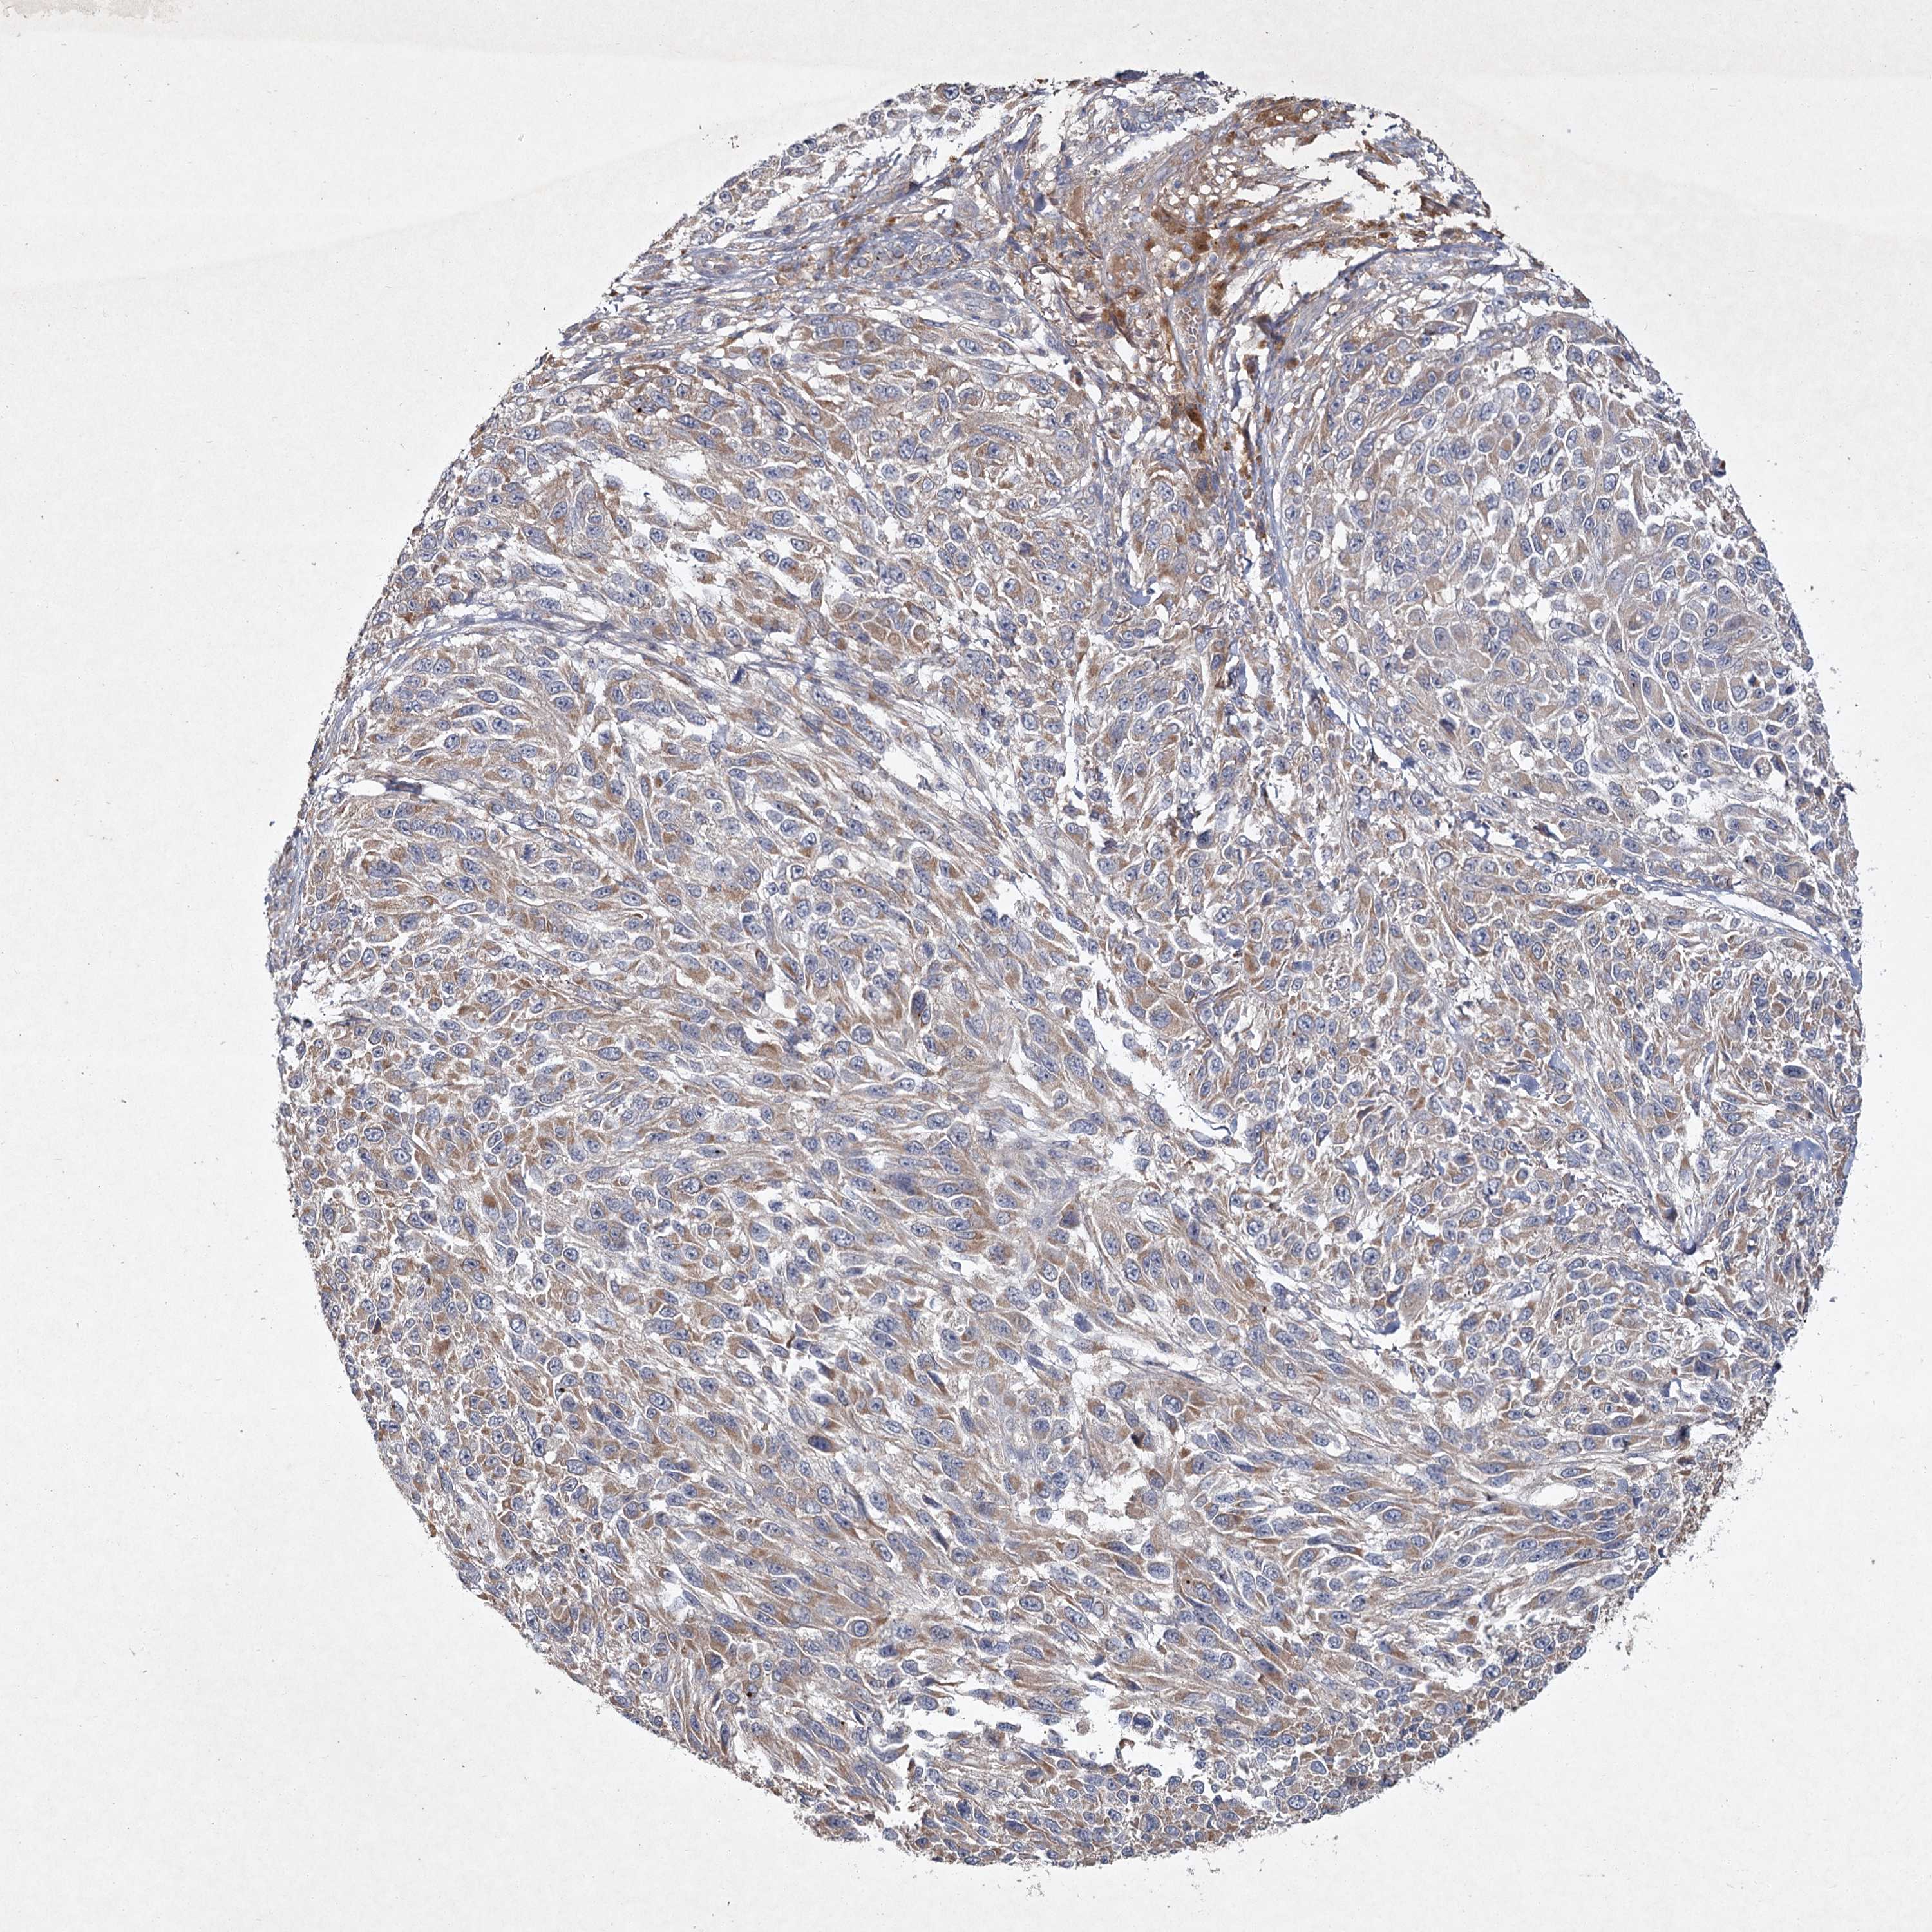

MELANOMA - Protein expressioni

A mouse-over function shows sample information and annotation data. Click on an image to view it in a full screen mode. Samples can be filtered based on level of antibody staining by selecting one or several of the following categories: high, medium, low and not detected. The assay and annotation is described here.

Note that samples used for immunohistochemistry by the Human Protein Atlas do not correspond to samples in the TCGA dataset.

Antibody stainingi

Antibody staining in the annotated cell types in the current human tissue is reported as not detected, low, medium, or high, based on conventional immunohistochemistry profiling in selected tissues. This score is based on the combination of the staining intensity and fraction of stained cells.

Each image is clickable and will lead to virtual microscopy that enables deeper exploration of all samples and also displays staining intensity scores, fraction scores and subcellular localization as well as patient and tissue information for each sample.

Antibody CAB033437

Staining

High

Medium

Low

Not detected

Intensity

Strong

Moderate

Weak

Negative

Quantity

>75%

75%-25%

<25%

None

Location

Nuclear

Cytoplasmic/membranous

Cytoplasmic/membranous,nuclear

Malignant melanoma, NOS

Malignant melanoma, Metastatic site